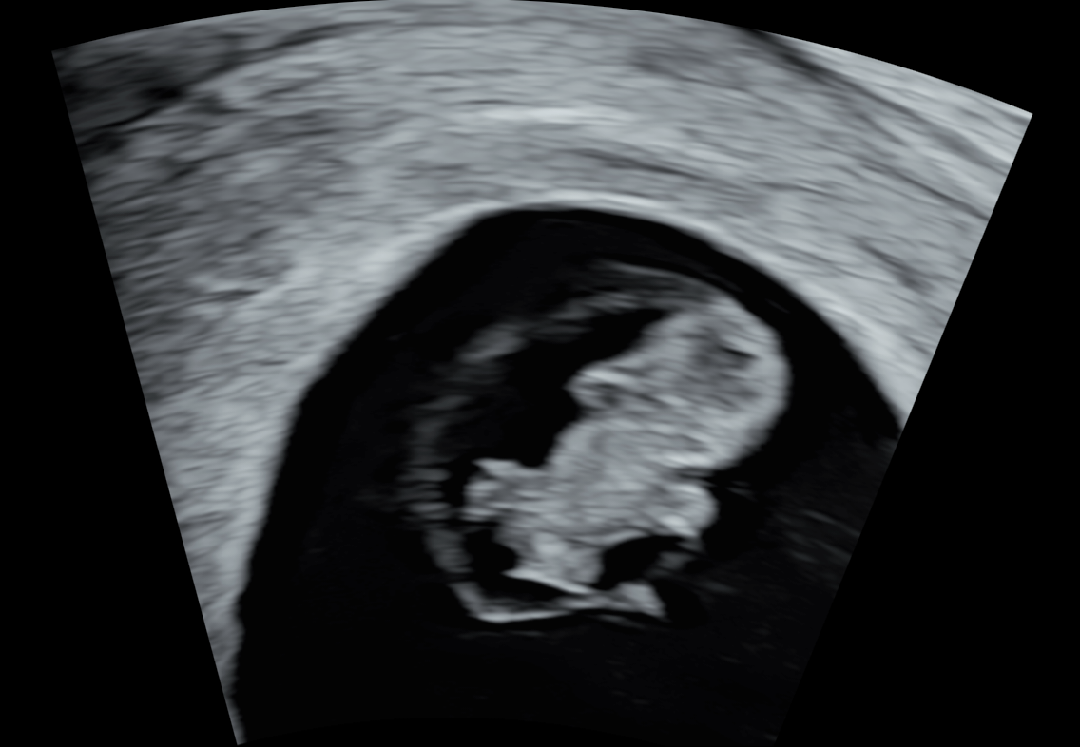

8주1일차 초진!!

사실 둘째를 가져서 넘 행복한데 두번의 유산경험이 있어서 그런지.. 초진전까지 걱정과 불안을 떨칠수가 없었어요ㅜ 오늘 드디어 아기를 만나고 왔는데 아이가 주수에 맞게 잘자라고 있고 심장도 잘뛴대서 너무 감사하네요ㅠㅠ 갑자기 두번보낸 아이들 생각이 나면서 감사의 눈물을 얼마나 흘렸는지 몰라요🥹 입덧때매 괴로워도 아이만 건강하다면 제몸 힘든건 상관없어요ㅎㅎㅎ 모두 만출까지 힘내시길 바라요💪💪🤗

네!! 젤리곰모양이 귀엽더라구요ㅎㅎ 그리고 벌써 아기가 움직이네요ㅎㅎ 참 신기했어요^^